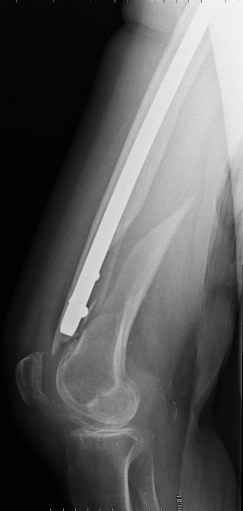

4. We could treat this fracture like there is no a nail - new locking plates allow for secure fixation.... two similar cases are attached...

Images sent by Professor Kanlic look nice, very good job. Excellent achorage in distal fragment. However, unicortical screwing or bicortical

makes a difference, also for locked screws. Proximal fragment unicortical fixation may present stability not easlily predictable. Certainly its stability for wheelchair should be sufficient. Full weight bearing can not be mentioned for this case. If minimal bearing is allowed full weight

Images sent by Professor Kanlic look nice, very good job. Excellent achorage in distal fragment. However, unicortical screwing or bicortical makes a difference, also for locked screws. Proximal fragment unicortical fixation may present stability not easlily predictable. Certainly its

stability for wheelchair should be sufficient. Full weight bearing can not be mentioned for this case. If minimal bearing is allowed full weight